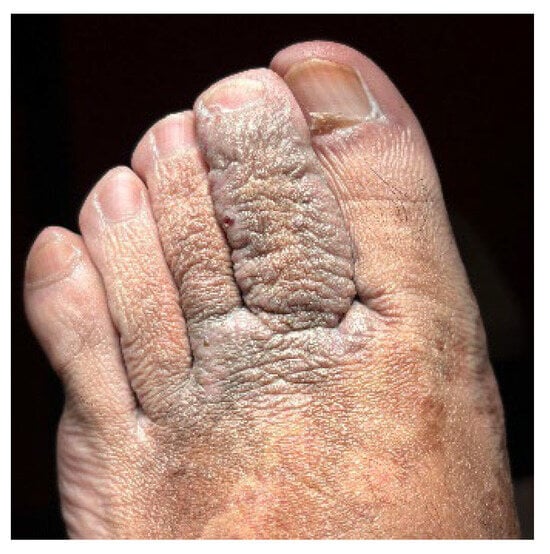

Unilateral Acroangiodermatitis: From Histopathologic Confirmation to Treatment with PDL

by André Aparício Martins, José Carlos Cardoso and André Pinho

Dermatopathology 2025, 12(4), 35; https://doi.org/10.3390/dermatopathology12040035 - 8 Oct 2025

Acroangiodermatitis is an uncommon angioproliferative dermatosis, related to chronic circulatory diseases, such as chronic venous insufficiency and arteriovenous malformations. We describe the case of a 32-year-old healthy male presenting with a pruritic, brownish lesion on the dorsal surface of the left foot, evolving [...] Read more.

Acroangiodermatitis is an uncommon angioproliferative dermatosis, related to chronic circulatory diseases, such as chronic venous insufficiency and arteriovenous malformations. We describe the case of a 32-year-old healthy male presenting with a pruritic, brownish lesion on the dorsal surface of the left foot, evolving for ten years. Physical examination revealed a brown plaque, with a verrucous surface, on the distal dorsum and medial border of the left foot. Histopathology disclosed a marked neovascularization of the upper dermis, associated with erythrocyte extravasation and hemosiderin deposition. Immunochemistry for HHV-8 was negative. CT angiography revealed multiple serpiginous vessels on the dorsum of the left foot, suggestive of a venous malformation. The diagnosis of acroangiodermatitis was established and the patient started topical corticosteroids and compression stockings, without improvement. Although scarcely described in the literature, treatment with PDL was proposed given the vascular proliferation confined to the papillary dermis. After two sessions, a significant improvement was observed. This case emphasises dermatopathology as the gold standard for the differential diagnosis with Kaposi sarcoma. In addition, it highlights PDL as a promising therapeutic option, based on the superficial histopathological location. Full article